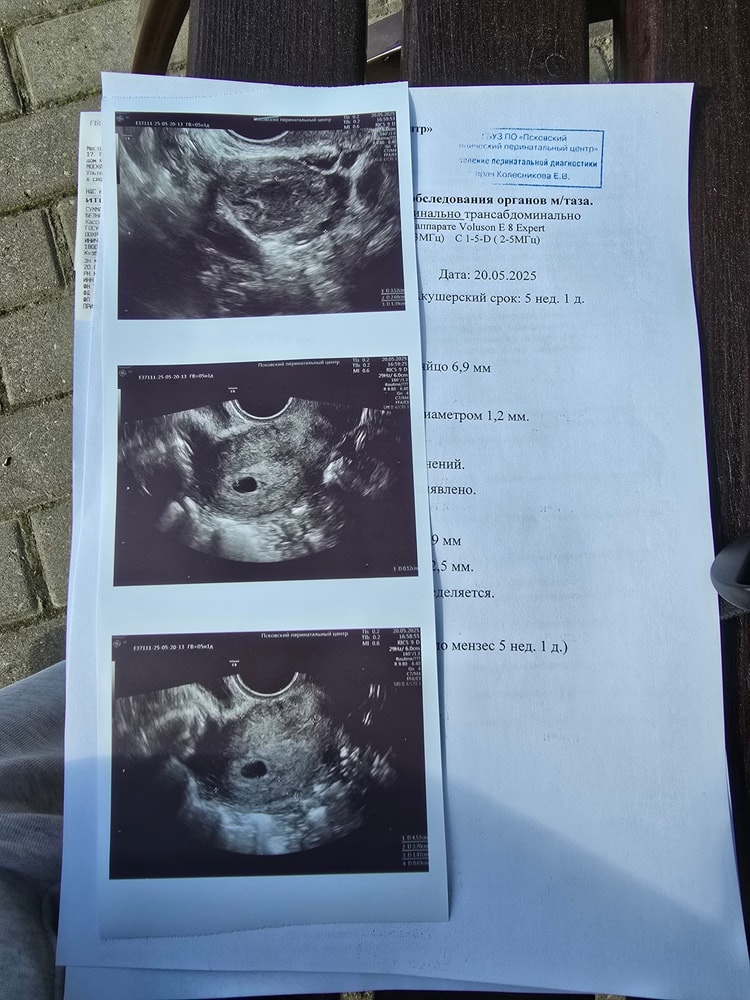

Узи 5 недель 1 день

Теперь я спокойна , я пошла что бы уточнить нету ли внематочной беременности 🤰

20.05.2025